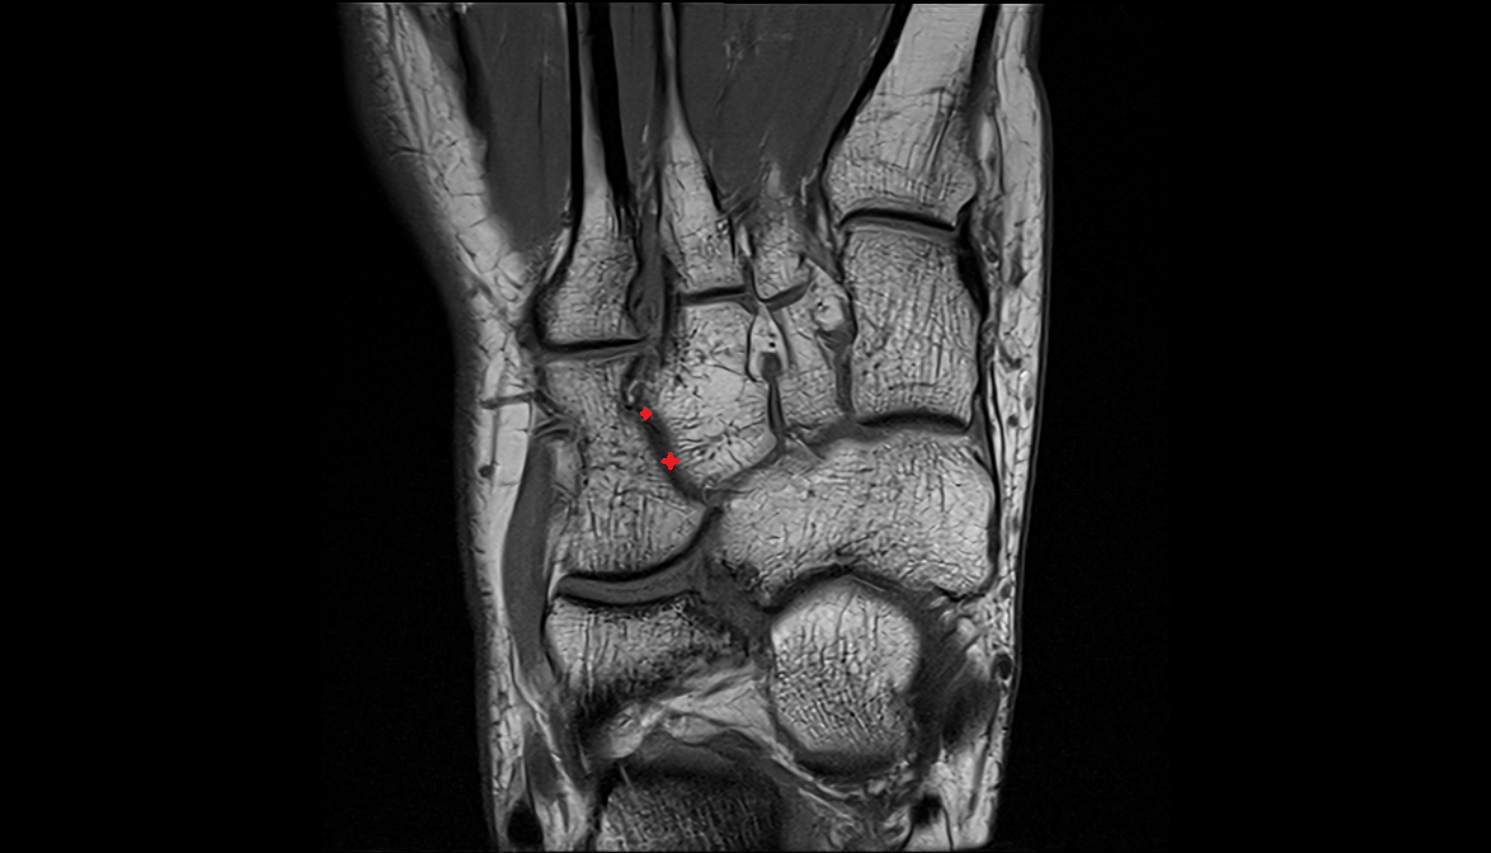

- Talus

- Head of talus

- Body of talus

- Neck of talus

- Calcaneus

- Anterior process of calcaneus

- Sustentaculum tali

- Tuberosity of navicular bone

- Medial malleolus

- Lateral malleolus

- Ankle joint

- Talocalcaneal joint

- Talocalcaneonavicular joint

- Calcaneocuboid joint

- Navicular bone